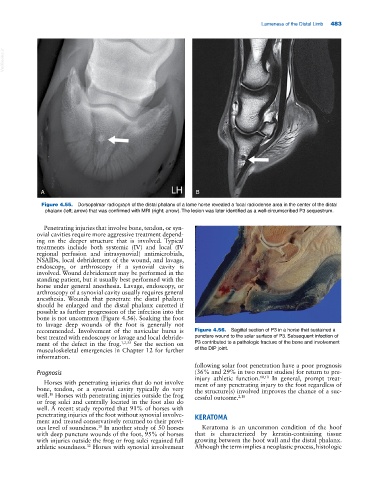

Figure 4.55. Dorsopalmar radiograph of the distal phalanx of a lame horse revealed a focal radiodense area in the center of the distal

phalanx (left; arrow) that was confirmed with MRI (right; arrow). The lesion was later identified as a well‐circumscribed P3 sequestrum.

recommended. Involvement of the navicular bursa is Figure 4.56. Sagittal section of P3 in a horse that sustained a

best treated with endoscopy or lavage and local debride- puncture wound to the solar surface of P3. Subsequent infection of

ment of the defect in the frog. 1,2,33 See the section on P3 contributed to a pathologic fracture of the bone and involvement

musculoskeletal emergencies in Chapter 12 for further of the DIP joint.